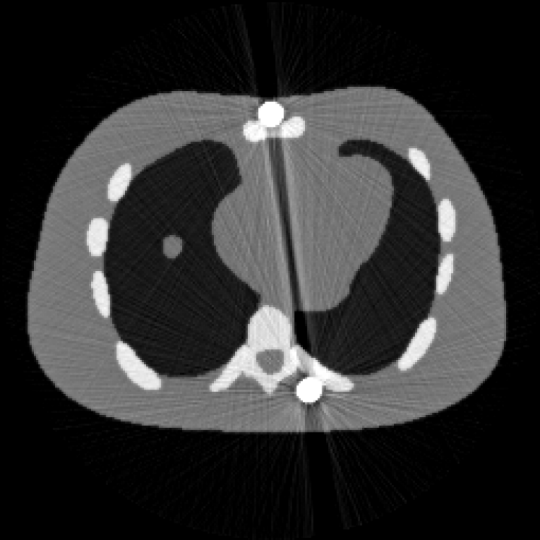

圖1 含金屬偽影的 NCAT圖像 圖2 校正后的NCAT 圖像

正則化強化邊界的對比度,引入圖像的有界性約束進一步提升重建精度。基于全變差的預對偶形式,設計了兩類有效且全局收斂的一階原對偶算法求解上述非凸模型。大量數值實驗結果驗證了該方法的有效性(圖1,圖2),特別在預分割不準確的情況下,所提出的算法的重建精度得到顯著提升。此外,所提出的全分裂算法比當前最具代表性的重加權JSR算法相比,計算速度平均提升兩倍。